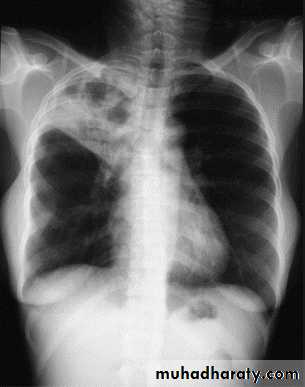

RLL collapse - PA.